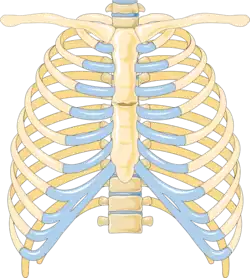

A sternal fracture is a fracture of the sternum (the breastbone), located in the center of the chest. The injury, which occurs in 5–8% of people who experience significant blunt chest trauma, may occur in vehicle accidents, when the still-moving chest strikes a steering wheel or dashboard[1] or is injured by a seatbelt. Cardiopulmonary resuscitation (CPR), has also been known to cause thoracic injury, including sternum and rib fractures. Sternal fractures may also occur as a pathological fracture, in people who have weakened bone in their sternum, due to another disease process.[2] Sternal fracture can interfere with breathing by making it more painful; however, its primary significance is that it can indicate the presence of serious associated internal injuries, especially to the heart and lungs.[3]

The upper and middle parts of the sternum are those most likely to fracture,[5] but most sternal fractures occur below the sternal angle.[1]